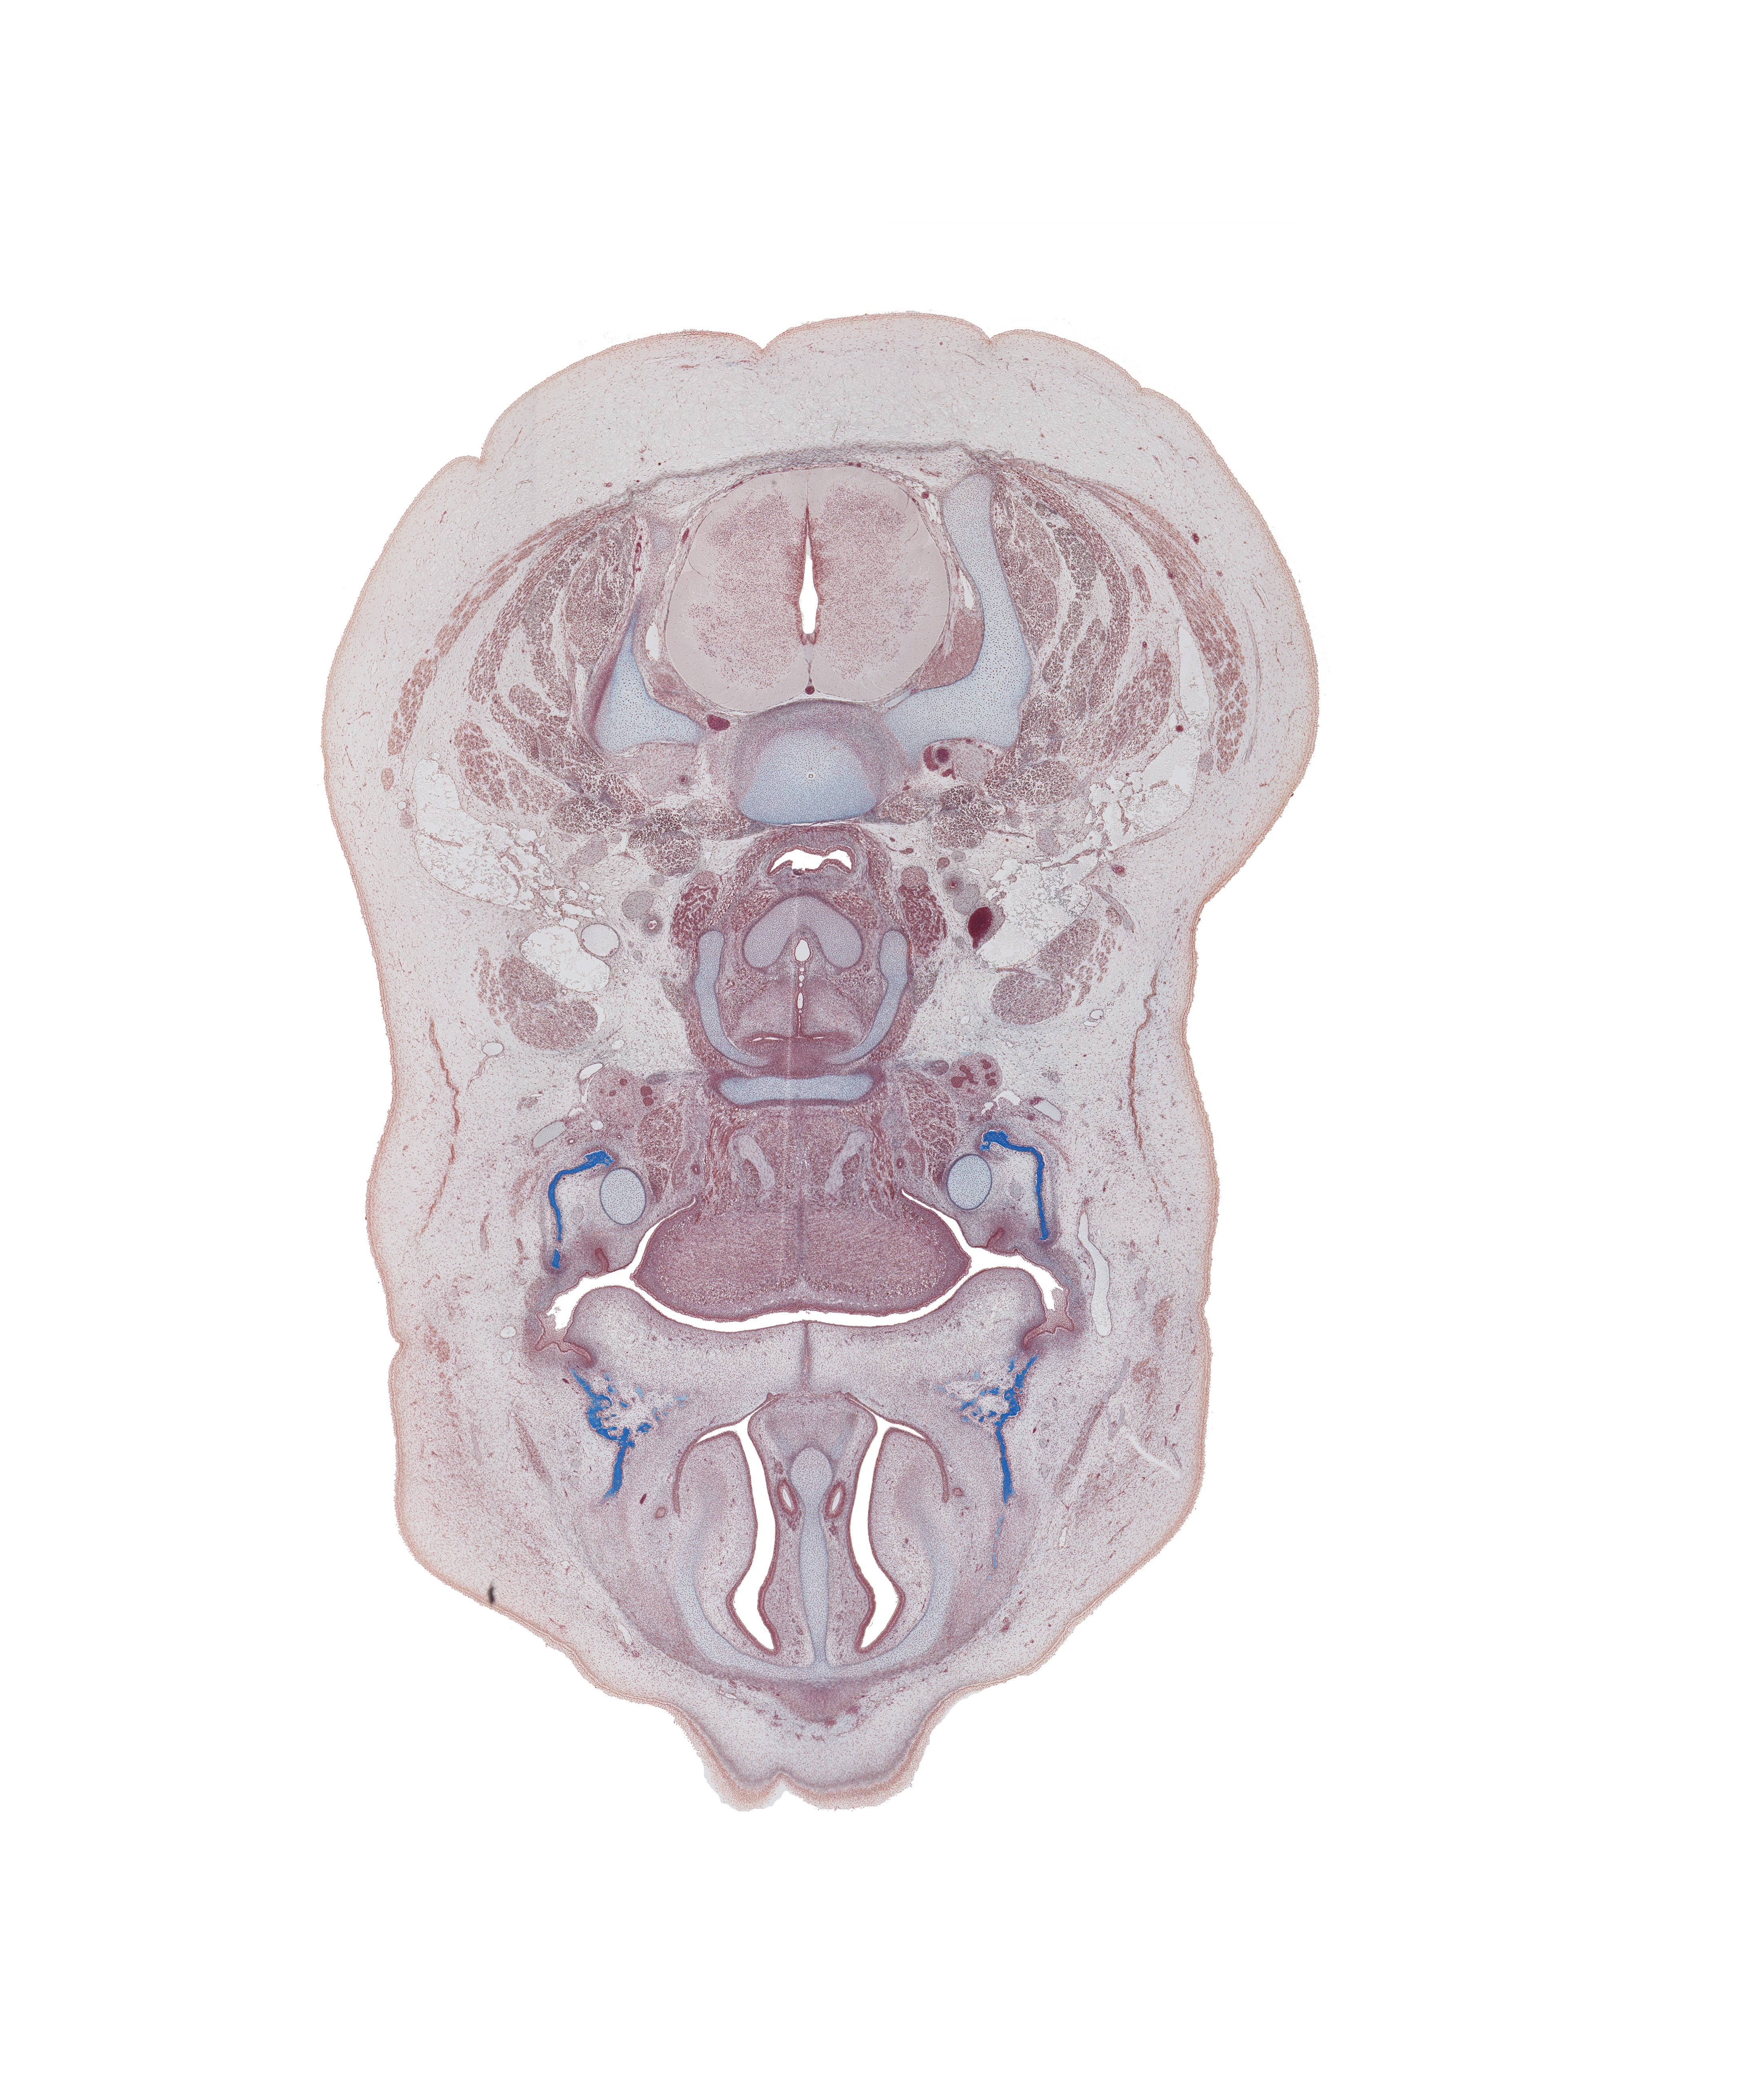

Carnegie Embryo #9226 | Location: 80-01-01

Keywords: C-5 / C-6 intervertebral disc, C-6 spinal ganglion, body of hyoid (pharyngeal arch 3 cartilage), central canal, cricoid cartilage, hypoglossal nerve (CN XII), inferior nasal concha, laryngeal pharynx, mandible ossification, maxilla ossification, middle cervical sympathetic ganglion, nasal septum, palatine shelf, superior parathyroid gland, thyroid cartilage, vertebral artery in transverse foramen, vomeronasal duct

Source: The Virtual Human Embryo.